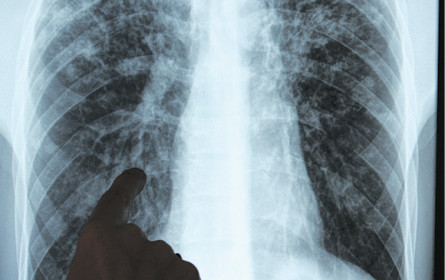

GENF/WIEN. Der Einbruch bei Entwicklungshilfegeldern bedroht den Erfolg im Kampf gegen Tuberkulose (TBC), die tödlichste Infektionskrankheit der Welt. Nach Angaben der Weltgesundheitsorganisation (WHO) sterben daran jedes Jahr 1,5 Mio. Menschen. Dennoch haben nun die USA unter Präsident Donald Trump Milliarden Dollar an Hilfsgeldern eingefroren. Aber auch andere Länder wie Großbritannien und Deutschland haben Einsparungen in der Entwicklungshilfe angekündigt.

Schon 2023 stand nur ein Viertel der benötigten 22 Mrd. USD für die TBC-Bekämpfung zur Verfügung. Mittlerweile droht in 27, vorwiegend ärmeren, Ländern ein Zusammenbruch der TBC-Programme, berichtet die WHO. „Es bedeutet das Aus für unzählige Tuberkuloseprogramme, durch die jedes Jahr Millionen Menschenleben gerettet werden”, sagt der Lungenexperte Meinhard Kneussl, Präsident des Österreichischen Tuberkulose Vereins. Auch Österreich drohen so neue Gefahren, etwa durch sich erhöhende Betroffenenraten in Migrationsgruppen und durch medikamentenresistente Tuberkulosebakterien. (red)